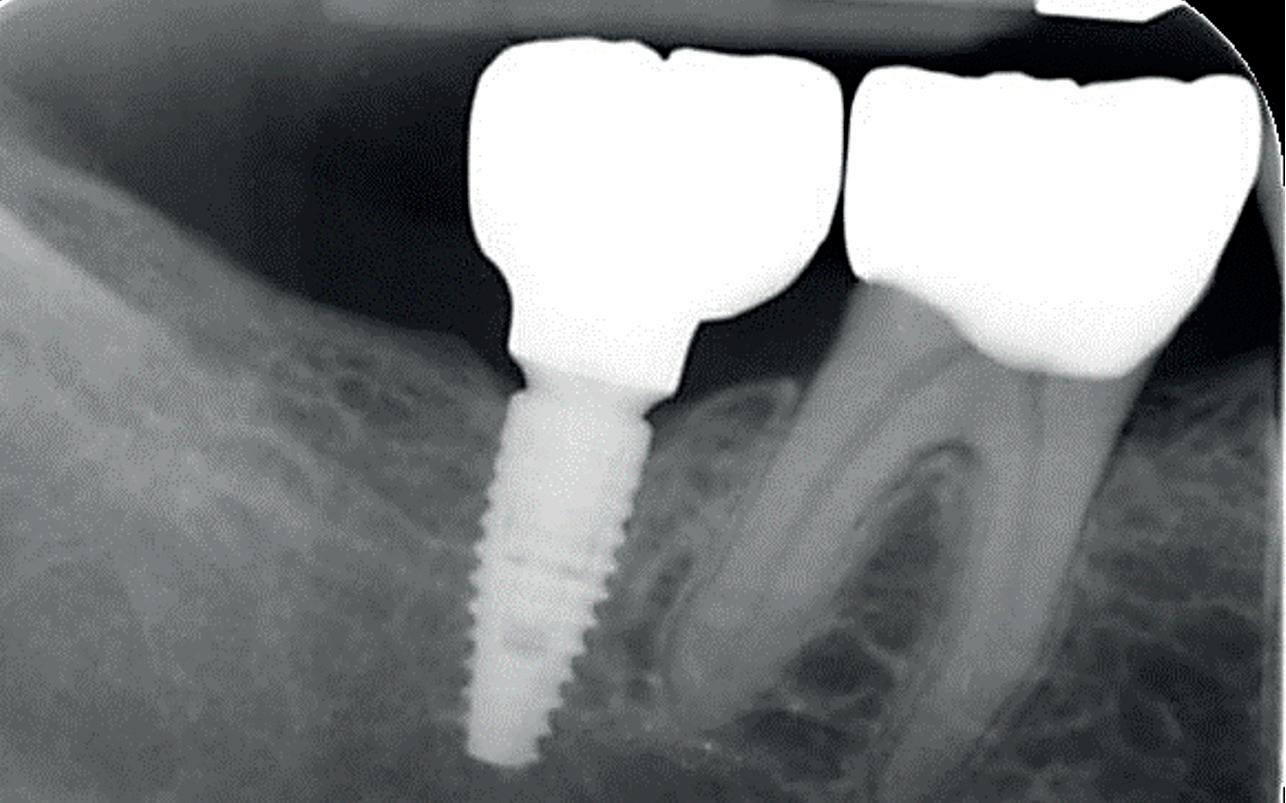

Bij klinisch en röntgenologisch onderzoek viel echter op dat radix van de 12 en 22 een convergerende (de radices staan dan naar mesiaal en naar elkaar toe) in plaats van divergerende (radices staan dan van elkaar af) stand had. Door deze convergerende stand van de radices was er in mesio-distale zin geen ruimte voor twee implantaten ter plaatse van de 11 en 21. Er werd daarom besloten, in tegenzin

1. Retainer met twee frontelementen

2. OPT radices 12 en 22 convergeren

3. Vaste apparatuur voor torque 12 en 22

4. OPT radices 12 en 22 divergeren na orthodontische behandeling

van de patiënt, om eerst weer vaste apparatuur terug te plaatsen om de radices in een divergerende stand te plaatsen. Gelukkig verliep deze behandeling voorspoedig. (afbeelding 2 -4). Het volgende behandelplan werd gemaakt: